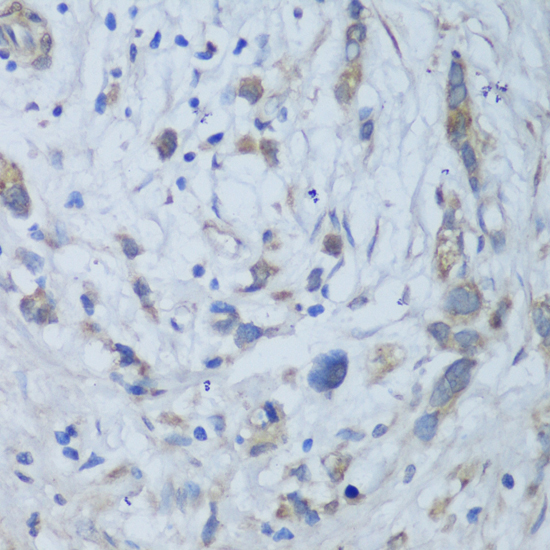

Immunohistochemistry - CEMIP Polyclonal Antibody

Immunohistochemistry of paraffin-embedded human gastric cancer using CEMIP antibody at dilution of 1:150 (40x lens).